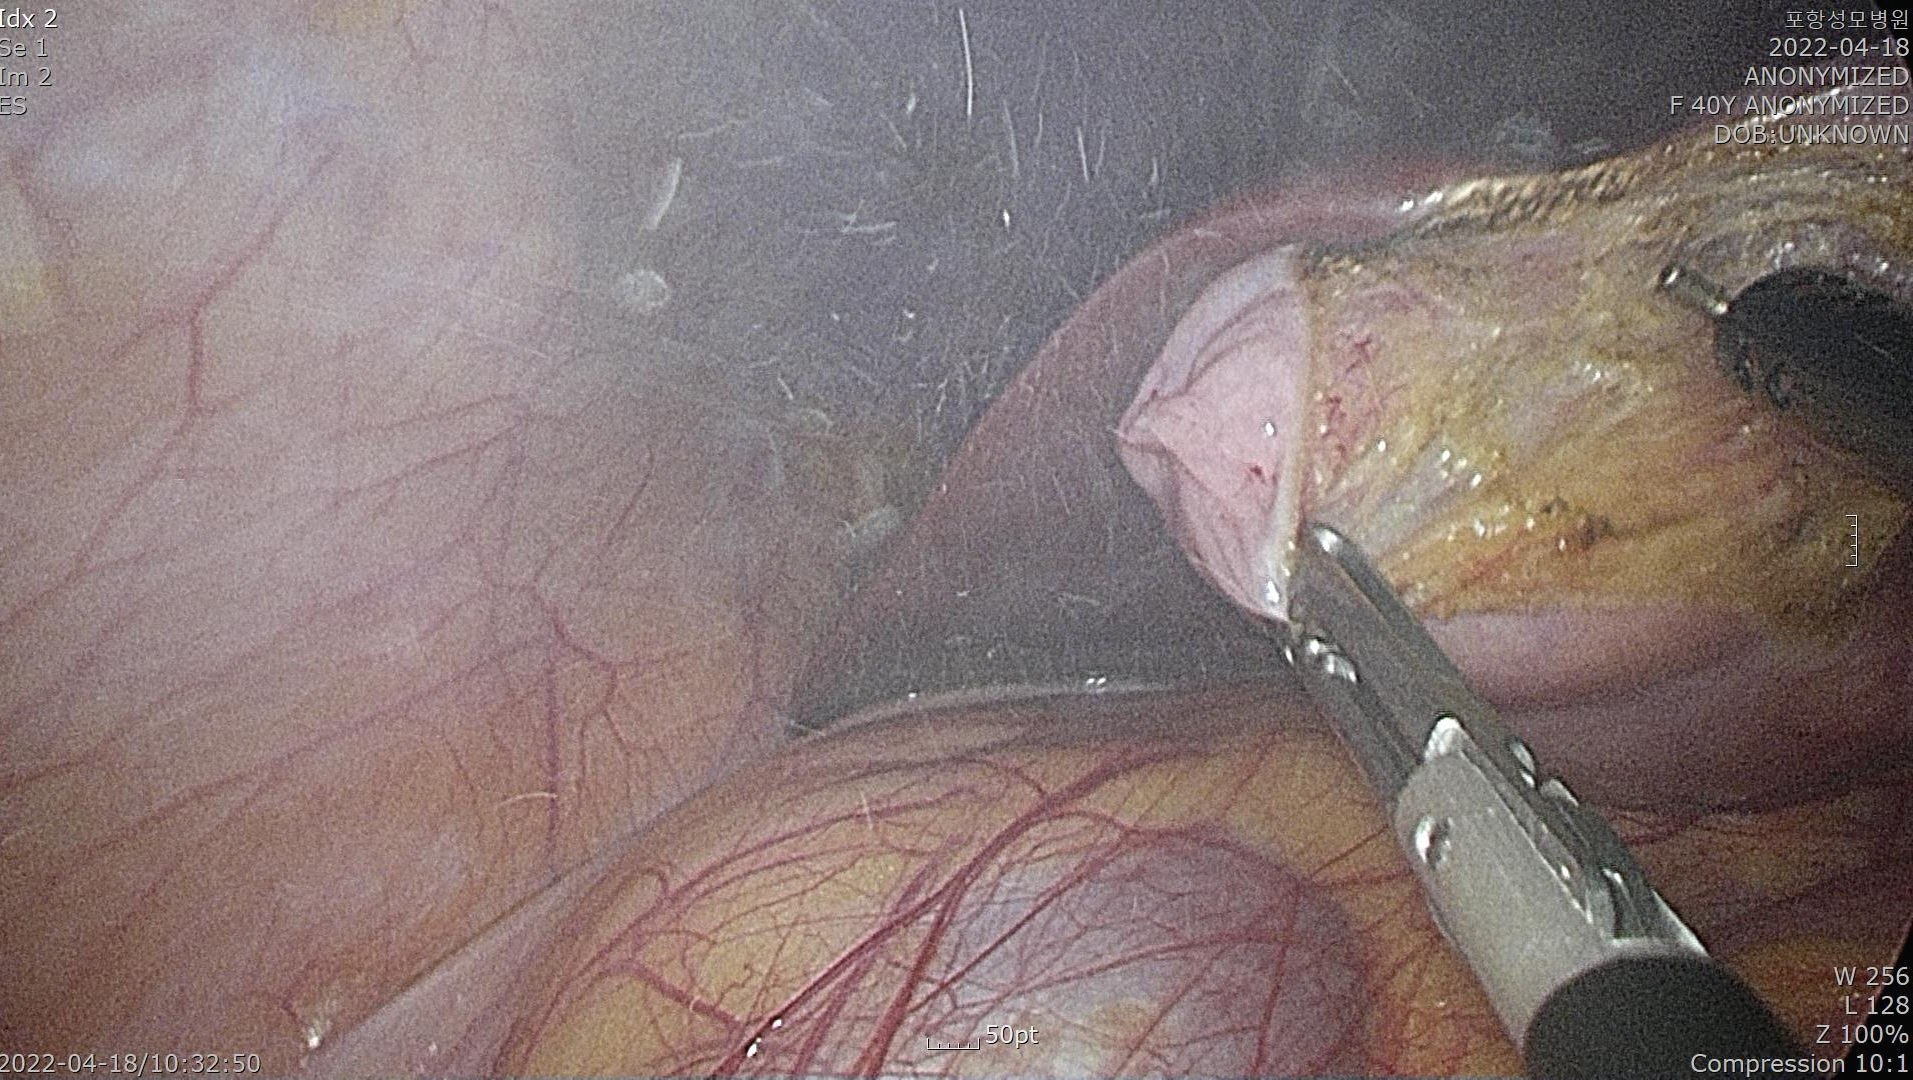

카메라로 복강내를 확인합니다.

담낭을 간 후벽으로 부터 절제해내고 있습니다. 단일공 복강경 담낭절제술은 섬세하고 정교한 수술 테크닉이 필요합니다.